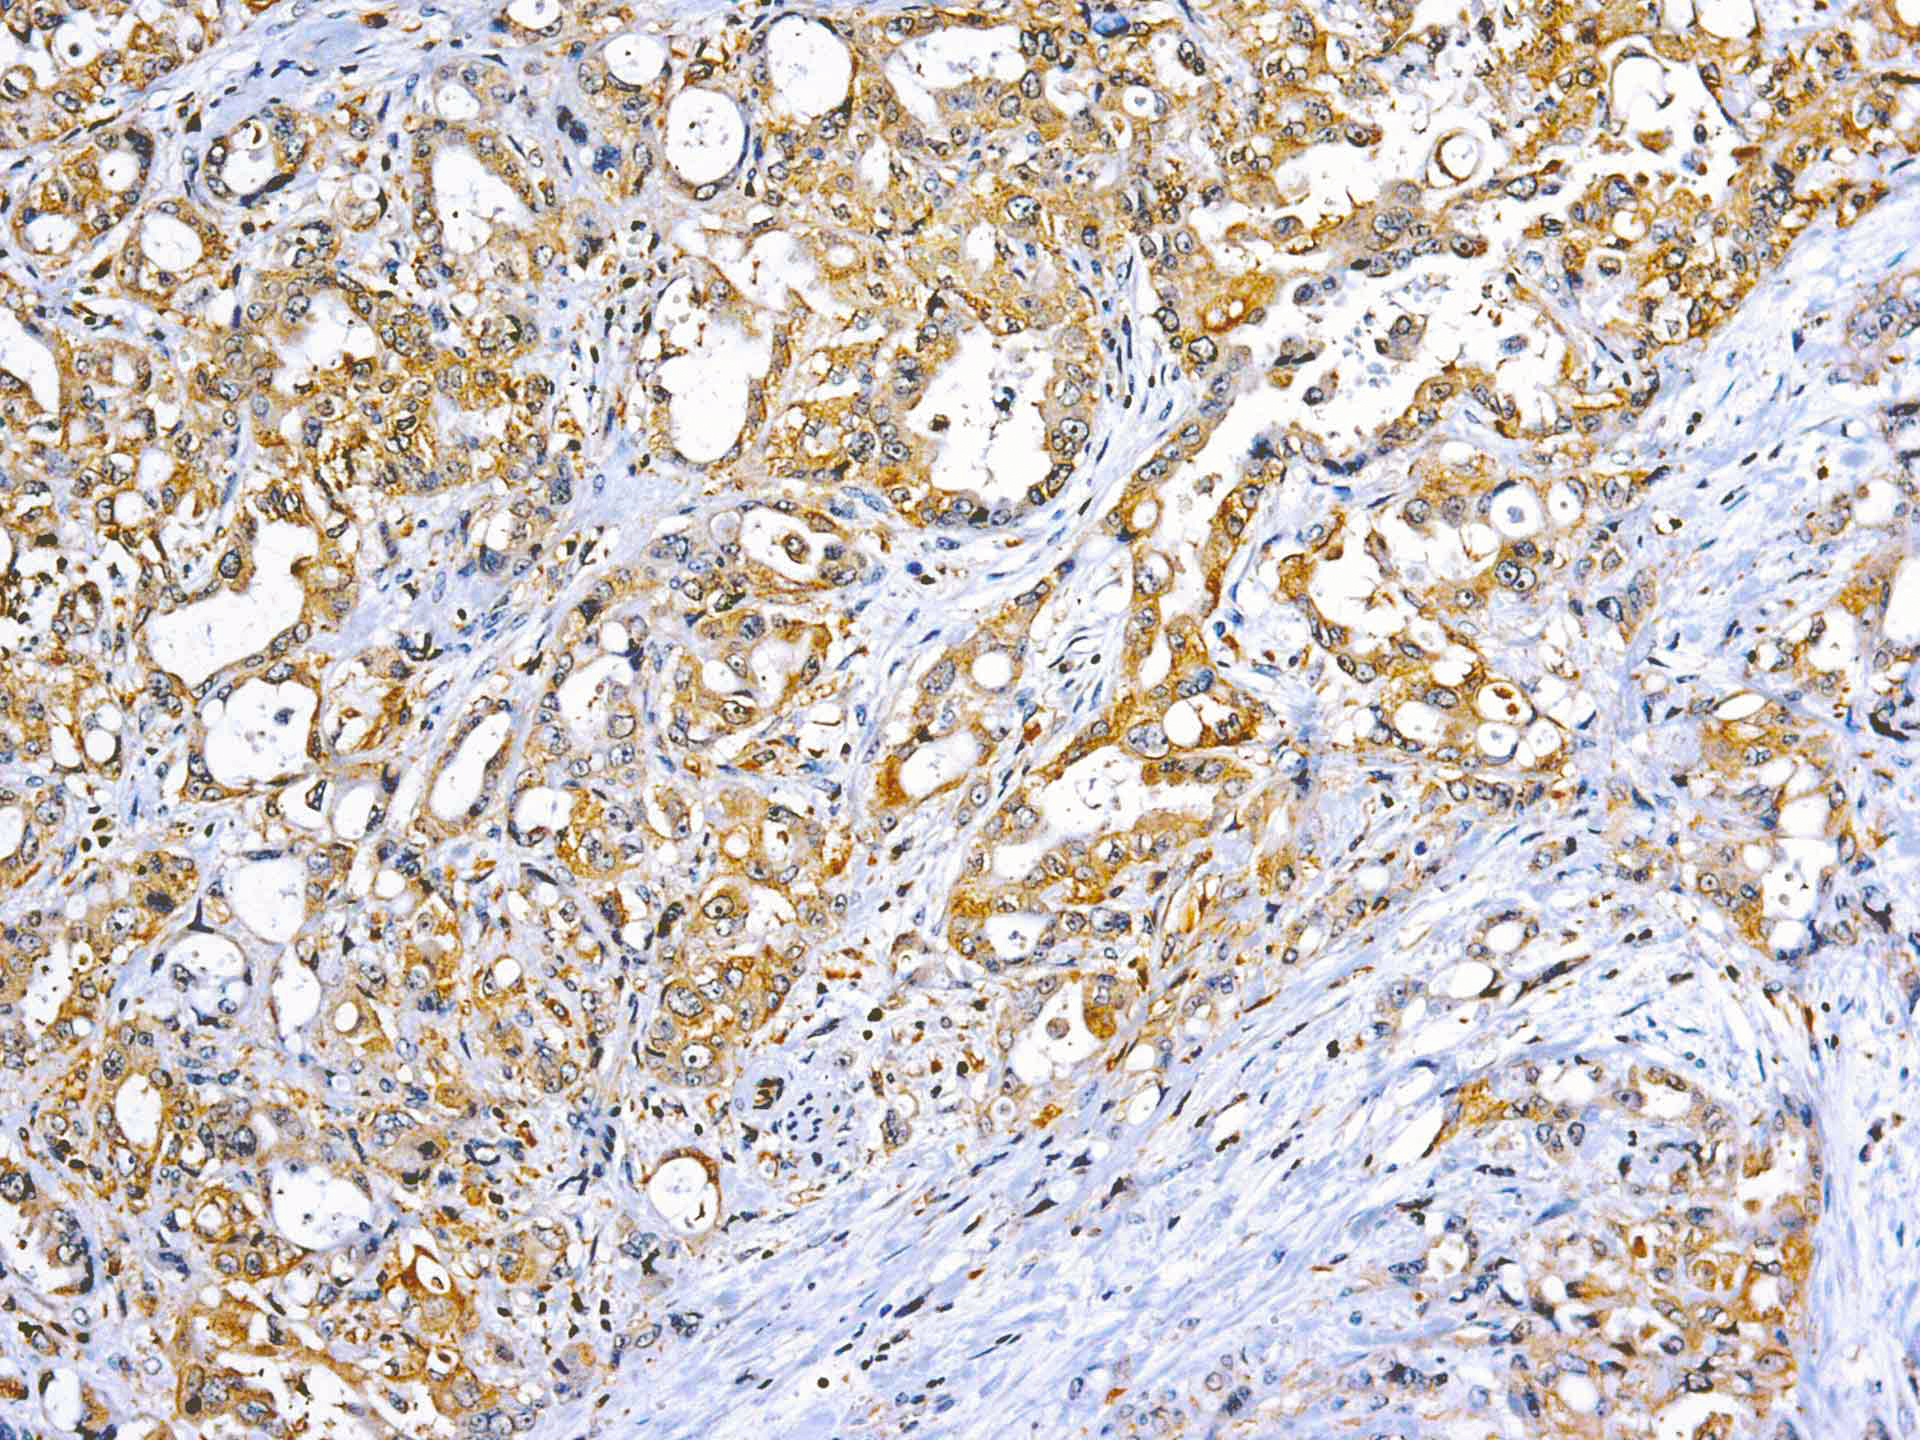

This MAb recognizes human 17-26kDa protein, which is identified as cytokine TNF-α (Tumor Necrosis Factor-alpha). Monomeric human TNF-α is a 157 amino acid protein (non-glycosylated) with a reported molecular weight of 17 kDa and can be expressed as a free molecule, also TNF-α is generated as a precursor form called transmembrane TNF-α can be expressed as a cell surface type II polypeptide consisting of 233 amino acid residues molecular weight 26 kDa. TNF-α is an important cell-signaling component of the immune system. It is a protein secreted by LPS stimulated macrophages, and causes tumor necrosis when injected into tumor bearing mice. TNF-α is currently being evaluated in treatment of certain cancers and AIDS Related Complex.

| Cellular Localization | Cytoplasmic and extracellular (secreted) |

| Positive Control Tissue | Colon, Histiocytoma, Pancreas |